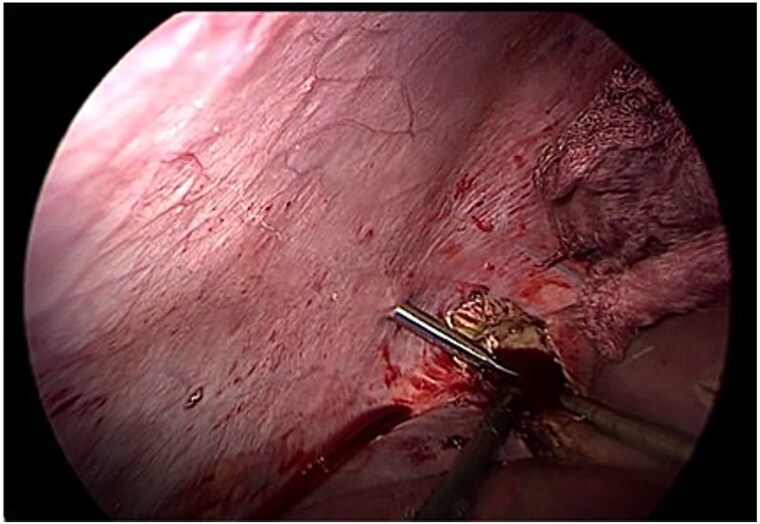

由细粒棘球绦虫引起的肝包虫病在流行地区仍然很流行。手术是治疗的基石,尽管在过去的十年中,腹腔镜方法在选定的病例中获得了突出的地位。我们提出一个病例的加尔比II型肝包虫囊肿成功地通过腹腔镜治疗。19岁男性,来自农村流行地区,表现为右上腹部疼痛。影像学显示肝后段VII有Gharbi 2型包虫囊肿。腹腔镜下对囊肿内容物进行了严格的预防措施,以避免播散。患者预后良好,无并发症。在经验丰富的中心,腹腔镜为没有胆道通信的周围囊肿提供了安全的选择。适当的患者选择和技术熟练程度对于最小化风险至关重要。本报告强调了在精心挑选的患者中腹腔镜治疗Gharbi II型囊肿的可行性,并说明了腹腔镜作为PAIR失败后的抢救策略的作用。

Hepatic hydatidosis, caused by Echinococcus granulosus, remains prevalent in endemic regions. Surgery is the cornerstone of treatment, although laparoscopic approaches have gained prominence in selected cases in the past decade. We present a case of a Gharbi-type II hepatic hydatid cyst successfully treated via laparoscopy. A 19-year-old man from a rural endemic area, presented with right upper quadrant pain. Imaging revealed a Gharbi type 2 hydatid cyst in the posterior segment VII of the liver. Laparoscopic evacuation of the cyst content was performed with strict preventive measures to avoid dissemination. The patient had a favorable outcome without complications. Laparoscopy offers a safe alternative for peripheral cysts without biliary communication and in experienced centers. Proper patient selection and technical proficiency are essential to minimize risks. This report highlights the feasibility of laparoscopic management of Gharbi type II cysts in carefully selected patients and illustrates the role of laparoscopy as a salvage strategy following failed PAIR.